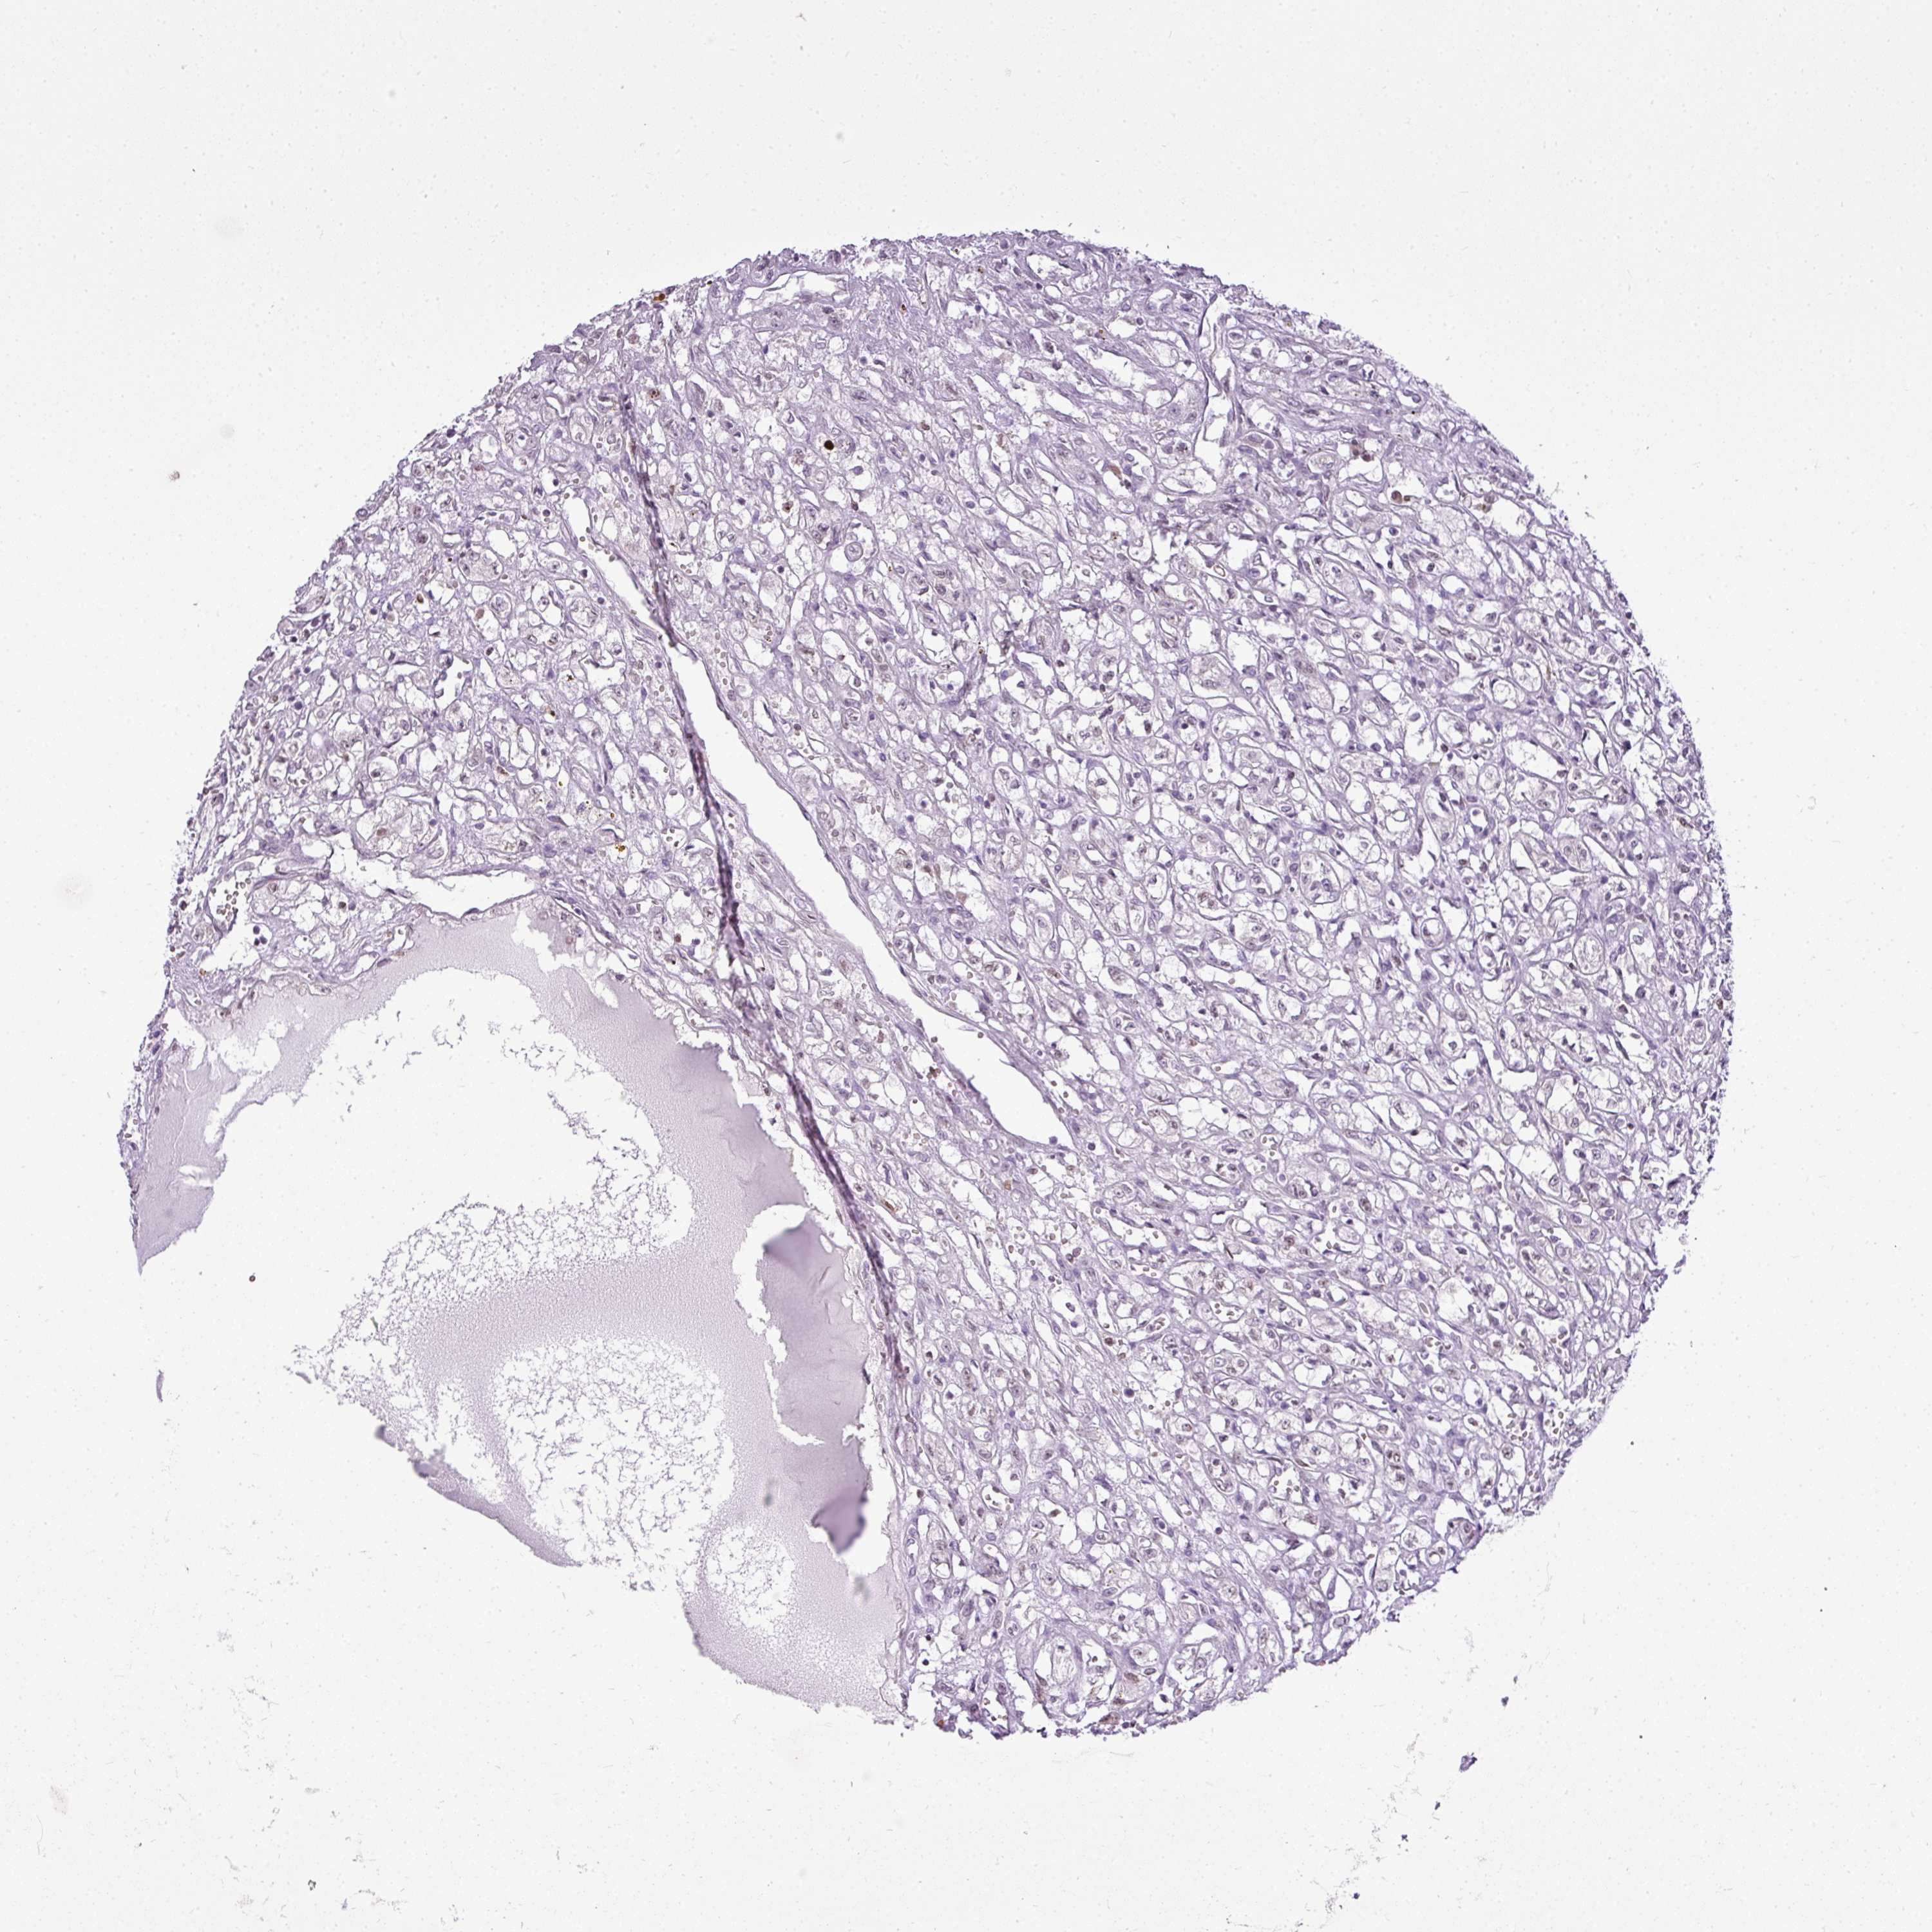

KIDNEY RENAL CLEAR CELL CARCINOMA (VALIDATION) - Interactive survival scatter ploti

The Survival Scatter plot shows the clinical status (i.e. dead or alive) for all individuals in the patient cohort, based on the same data that underlies the corresponding Kaplan-Meier plots. Patients that are alive at last time for follow-up are shown in blue and patients who have died during the study are shown in red.

& Survival analysisi

Kaplan-Meier plots summarize results from analysis of correlation between mRNA expression level and patient survival. Patients were divided based on level of expression into one of the two groups "low" (under cut off) or "high" (over cut off). X-axis shows time for survival (years) and y-axis shows the probability of survival, where 1.0 corresponds to 100 percent.

COX18 is not prognostic in Kidney Renal Clear Cell Carcinoma (validation)

TCGA RNA samplesi

RNA-seq data is reported as average FPKM (number Fragments Per Kilobase of exon per Million reads), generated by the The Cancer Genome Atlas (TCGA) .

Normal distribution across the dataset is visualized with box plots, shown as median and 25th and 75th percentiles. Points are displayed as outliers if they are above or below 1.5 times the interquartile range. FPKM values of the individual samples are presented next to the box plot.

Average pTPM 0.9

Number of samples 100